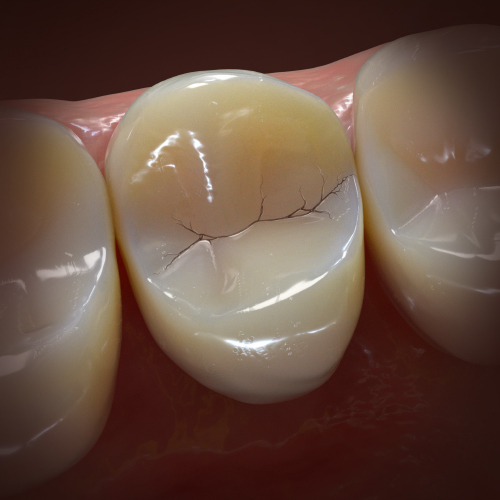

Early Diagnosis and Treatment of Asymptomatic Vertical Enamel and Dentin Cracks

Samer S. Alassaad, DDS

Wednesday, November 23, 2022

This Compendium eBook offers a continuing education (CE) article that presents a systematic approach for the early diagnosis and treatment of asymptomatic vertical enamel and dentin cracks based on current evidence. Download to earn 2 FREE CEU now!

Current Topics in Restorative Dentistry

Monday, February 26, 2018

This Compendium eBook provides two continuing education articles on restorative dentistry, each focusing on topics related specifically to enamel. In the first CE, the author offers a systematic approach for early intervention for asymptomatic vertical enamel and dentin cracks based on current evide...